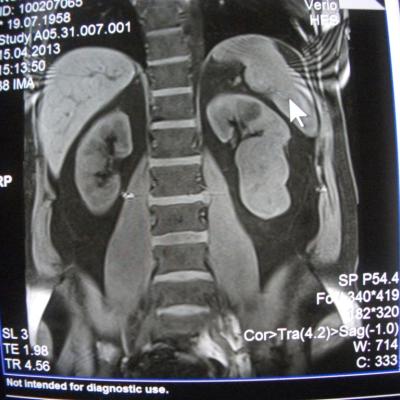

такое заключение: Левая почка: расположена обычно, увеличена, общими размерами около 13х5,5см. В области средней и нижней трети почки определяется объёмное образование неправильной формы, деформирующее наружный контур почки, распространяющиеся с чашечно-лоханочную систему. Опухоль имеет четкие неровные бугристые контуры с наличием псевдокапсулы, неоднородной структуры с признаками распада, максимальными размерами около 78,7х47х48мм